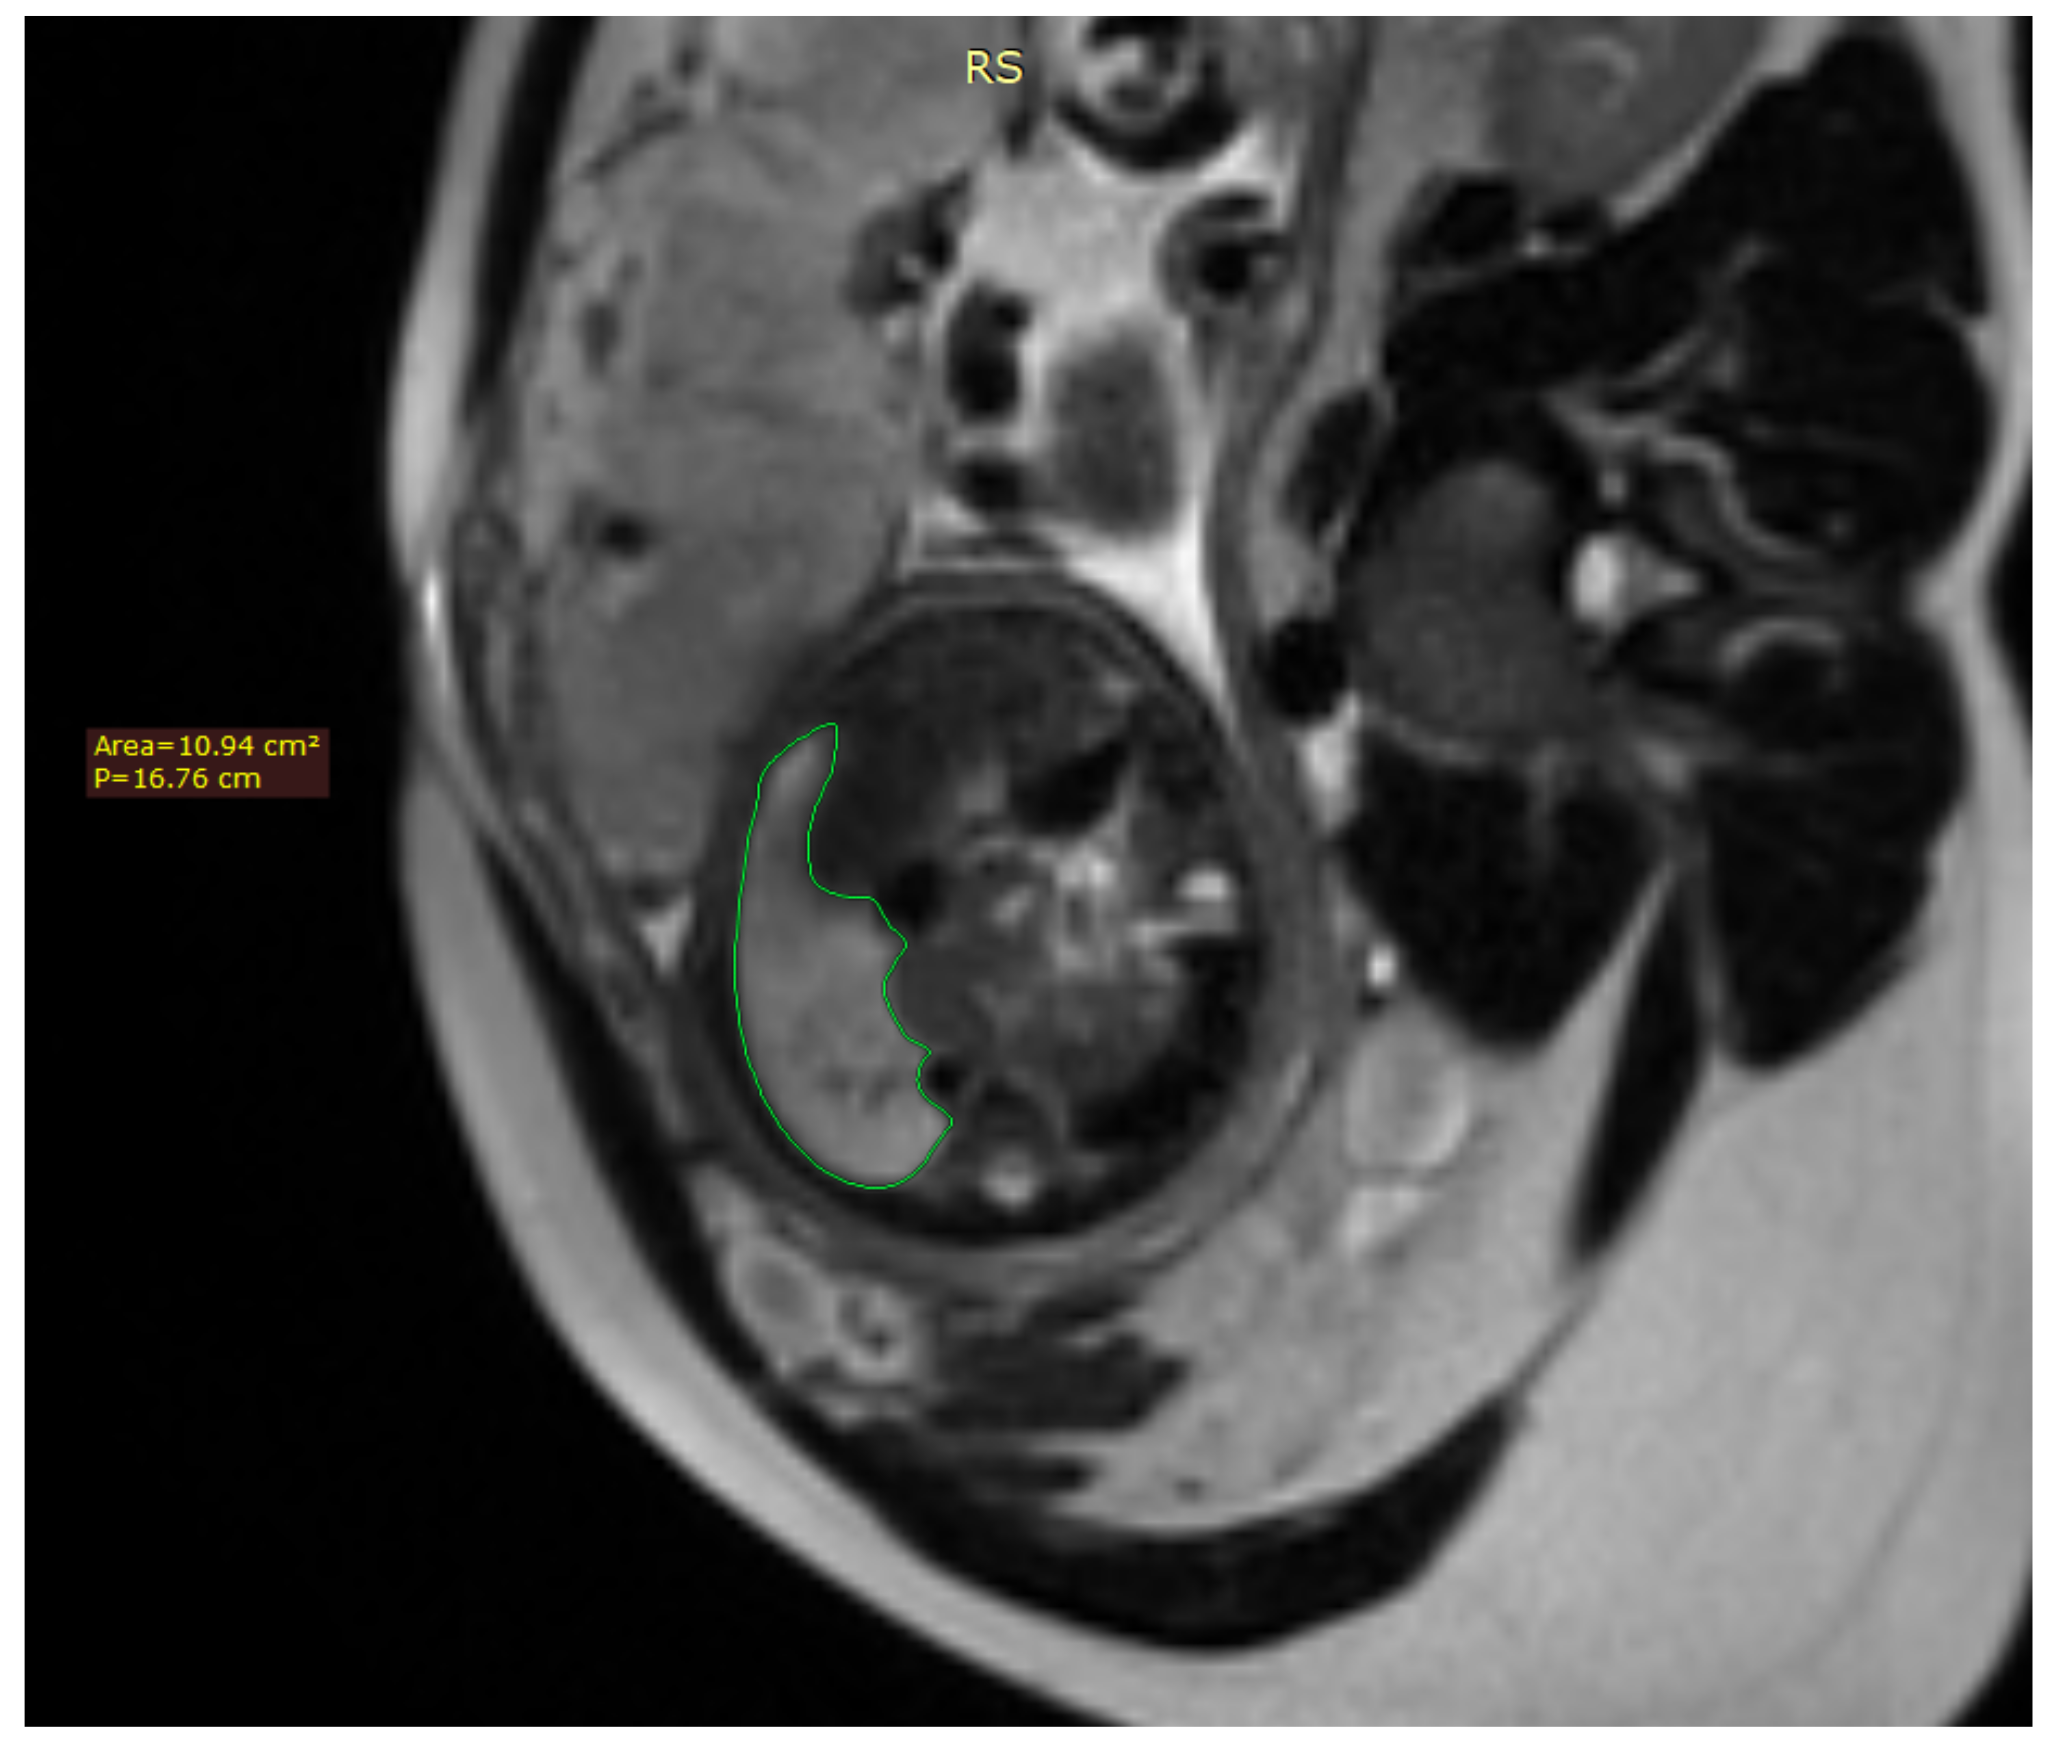

Fetal lung volume was calculated by tracing the lung area of each slice and multiplying it by the thickness between the slices, whilst also accounting for the overlap of the slices. We used the usual DICOM viewing software such as RadiAnt DICOM Viewer Figure 1.

Figure 1. Axial image of the fetus showing the tracing method for calculating the lung volume, using the RadiAnt DICOM Viewer program.